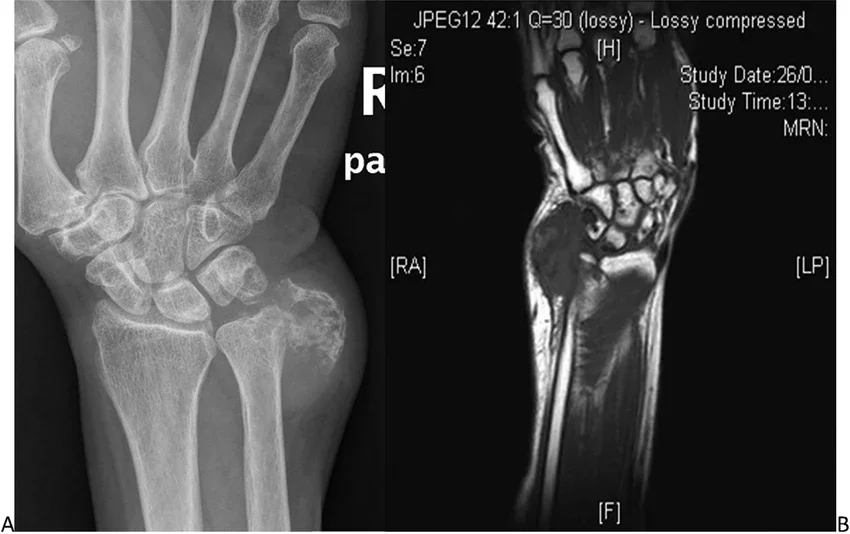

Образните изследвания имат ключова роля в диагностичния процес, като първото и най-често използвано изследване е рентгенографията. Типични находки при хондром са добре ограничена, просветлена зона в костта, наличие на калцификати в тумора и изтъняване на кортикалиса без ясно разрушаване.

Изображение: Хондрома на меките тъкани по улнарната страна на китката. (A) Рентгеновата снимка, показваща калцифицирана мекотъканна маса. (B) Магнитно-резонансната томография, показваща добре дефинирана мекотъканна маса. Източник: www.researchgate.net под лиценз: Creative Commons Attribution-NonCommercial-NoDerivatives 4.0 International

Компютърната томография има по-всиок визуализационен потенциал и често се назначава допълнително при неясни случаи или при планиране на хирургично лечение.

Ядрено-магнитен резонанс е особено полезен за оценка на размера на тумора, връзката му с околните меки тъкани, както и при подозрение за малигнена трансформация.